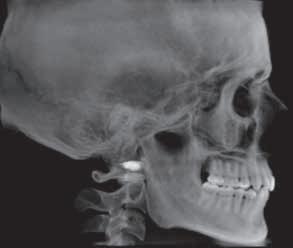

Clinical History:

A 24-year-old Asian American female presented for routine oral examination and prophylaxis. Her past medical history included papillary thyroid carcinoma (treated by partial left thyroidectomy 4 years prior), bilateral sensorineural and conductive hearing loss (since birth), enlarged vestibular aqueducts, childhood ear infections, scoliosis, acne, and attention-deficit/ hyperactivity disorder. The patient’s medications included azithromycin, spironolactone, and lisdexamfetamine. She reported an allergy to sulfa drugs. She had no history of tobacco or alcohol use. Her family history was negative for any heritable disorders or developmental conditions.

Upon clinical examination, you notice the unusual appearance of the corners of the patient’s mouth (Figure 1). No other significant oral anomalies are identified.

What is the diagnosis for this oral finding?

See page 264 for the answer and discussion.